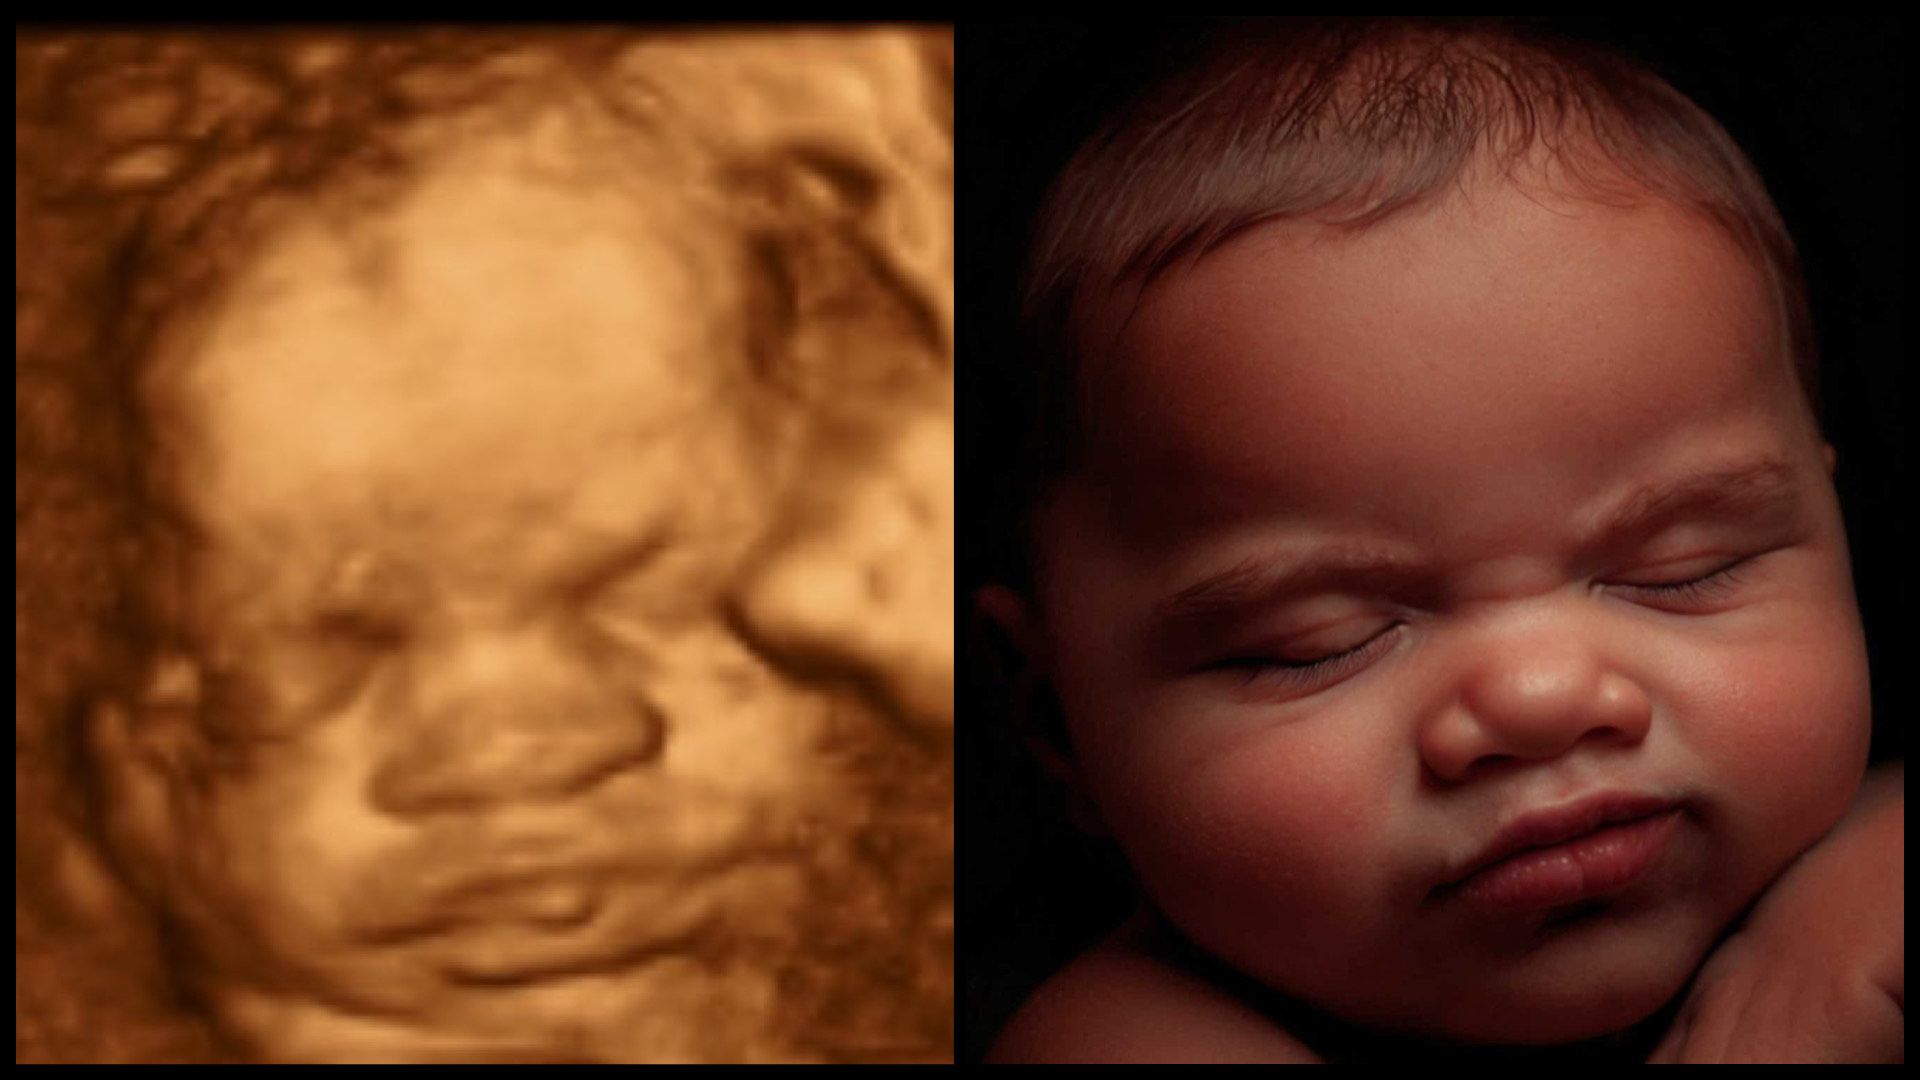

Most Realistic & lifelike photo you can get until the arrival of your little one. Using the newest technology to change your 3d/4d photo into something more realistic without changing any of your baby's features.